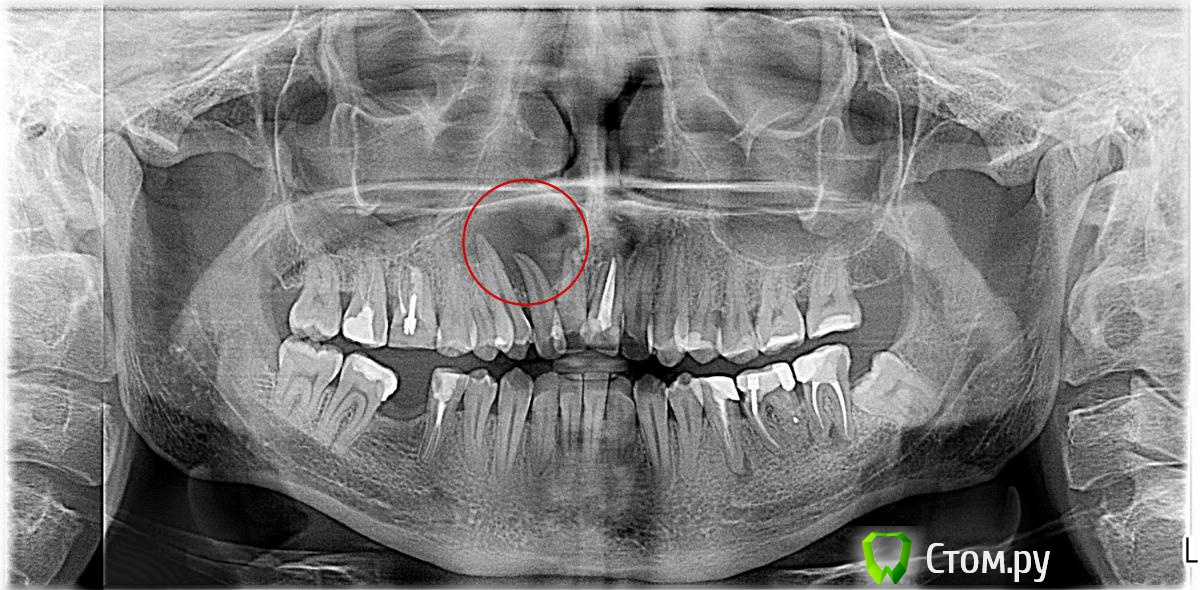

anima-animus Опубликовано 22 июля, 2014 Поделиться Опубликовано 22 июля, 2014 Доктора, посоветуйте, стоит ли пытаться вылечить зуб консервативно? Периодонтитной симптоматики нет, зуб неподвижен. Скученность зубов, тройка толкает двойку.Чем попробовать вылечить? Или лучше к хирургу? Ссылка на комментарий

sydnik Опубликовано 22 июля, 2014 Поделиться Опубликовано 22 июля, 2014 (изменено) консервативно не получится,по снимку 3 зуба вовлечены в процесс( возможно, какой-то из зубов останется живым). надо сделать кт и к хирургу на консультацию, там и решится судьба зубов Изменено 22 июля, 2014 пользователем sydnik Ссылка на комментарий

Cleric Опубликовано 23 июля, 2014 Поделиться Опубликовано 23 июля, 2014 (изменено) консервативно не получится,по снимку 3 зуба вовлечены в процесс( возможно, какой-то из зубов останется живым). надо сделать кт и к хирургу на консультацию, там и решится судьба зубов 12 ,скорее всего, на extr. Соседние-депульпировать и резекция. Успехов!Откуда только черпаете "знания", чтобы принимать такие варварские решения в банальном эндодонтическом случае? Любое радиолюцентное поражение у верхушки корня (естественно, об экзотических случаях речь не идет) по рентген снимку "по умолчанию" - апикальная гранулема и должна лечиться КОНСЕРВАТИВНО. При отсутствии положительной динамики (а в случае с первичной эндодонтией неудач мало) - апикальная хирургия с резекцией и ретроградной обтурацией. Но для начала, как уже было сказано ранее, необходимо определить причинный зуб. Изменено 23 июля, 2014 пользователем Cleric Ссылка на комментарий

Мартовский Опубликовано 24 июля, 2014 Поделиться Опубликовано 24 июля, 2014 Коллеги, те кто "за хирургию" - здесь привыкли что врачи свое мнение обосновывают, а вы предлагаете пациенту идти под нож, депульпировать не только причинный зуб и даже лишиться зуба в эстетически значимой зоне и не приводите доводов. Ждем от вас аргументов2Cleric - все таки расхождение зубов свидетельствует в пользу кисты, она растет компрессионно, и гранулема остекластически. Имхо конечно. Ссылка на комментарий

sydnik Опубликовано 24 июля, 2014 Поделиться Опубликовано 24 июля, 2014 (изменено) Коллеги,и Соломонова слушал и все по эндо перечитал на форуме(на соседнем тоже ) и книг много умных,но в данном случае смущают размеры кисты, тонюсенькие межзубные перегородки(в области двойки) и ,как мне кажется, дивергенция корней зубов+ всевозможные апикальные ответвления(в которых могут задержаться паразиты)вот собственно все это и натолкнуло о резекции.При резекции не обязательно убирать пол корня (,достаточно 3-4 мм, не помню где читал.) и лишать впоследствии пац драгоценного зуба. псИз утверждения и отрицания рождается истина. Изменено 24 июля, 2014 пользователем sydnik Ссылка на комментарий